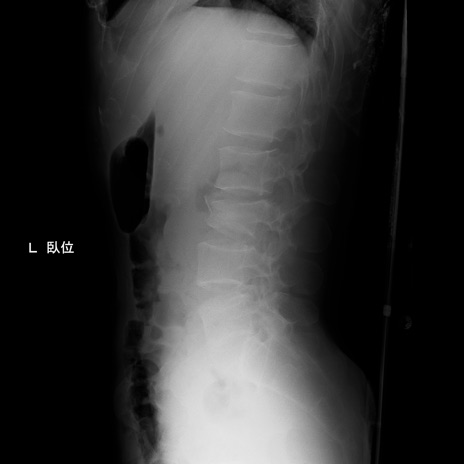

症例3 腰椎レントゲン(側面像)

【症例】30歳代男性

【主訴】腰痛

【現病歴】本日旅行先で観光中に、友人と衝突し転倒し受傷。

【身体所見】麻痺なし、右下腿内側前面外側、左下腿内側に知覚鈍麻・しびれ

異常所見と診断は?

腰椎レントゲン